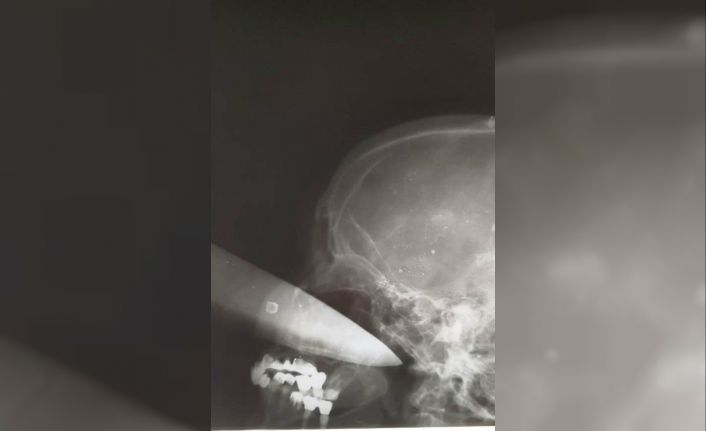

Bilinci yerinde olan kadın ameliyata alındı. Doktorların uzun süren çabasıyla kadının gözüne saplanan bıçak çıkarıldı. Bıçağın kadının gözünden 25 santimetre içeri girdiği belirtildi. Talihsiz kadın bıçağın saplandığı gözünü kaybetti.